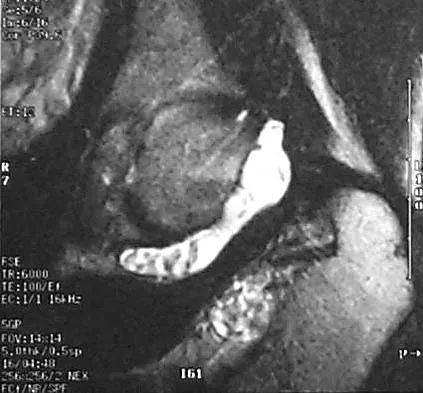

Figure 6 shows a sagittal oblique MRI scan. The arrow is pointing to what structure?

Detailed Explanation